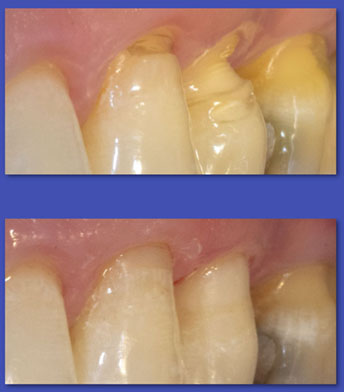

1.  OPERATORIA DENTAL

La Operatoria Dental se dedica a la restauración de los dientes dañados en forma parcial producto de caries, traumatismos  y otras lesiones no cariosas (atrición, abrasión, erosión, hipoplasias de esmalte, etc.). Hoy en día estas restauraciones se realizan en material de resina llamados “composite” que imitan el color del diente y han dejado casi obsoletas a las restauraciones metálicas y amalgamas.

ANTES

DESPUÉS